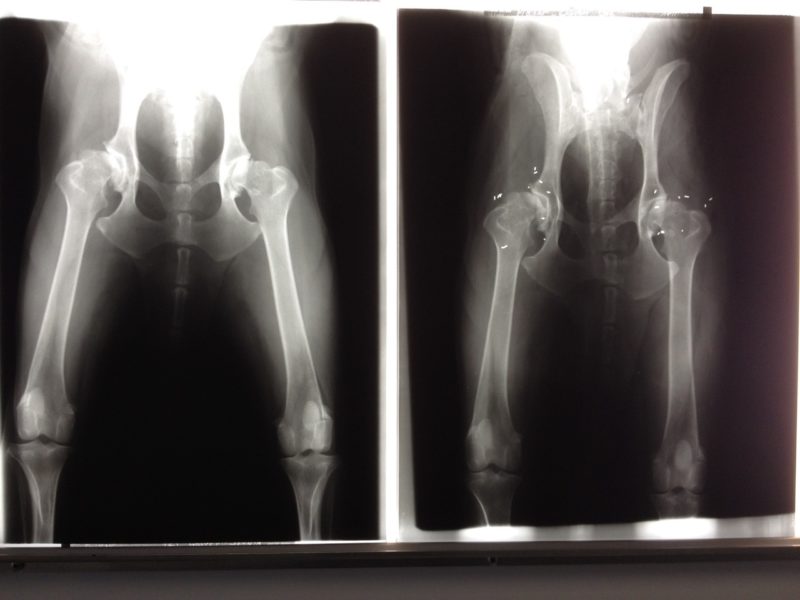

Dustin ist ein 12-jähriger Bearded Colli, der unter einer zunehmenden Schmerzsymptomatik litt. Die schmerzfreien Intervalle wurden immer kürzer. Dustin war ein jahrelanger Patient von mir, der aber mittlerweile durch einen berufsbedingten Umzug in 500 km Entfernung wohnt. Sein Frauchen arbeitet in der Altenpflege und nutzt Dustin als eine Art Therapiehund bei älteren Pflegeheimbewohnern. Aber auch das machte Dustin keinen Spass mehr. Das Aufstehen und Laufen fielen ihm zusehends schwerer. Die verabreichten Schmerzmittel wirkten nur noch bedingt. So konnte es nicht weitergehen. Dustin wurde dem Haustierarzt vorgestellt. Dieser riet nach einer klinischen und röntgenologischer Untersuchung und Rücksprache mit einer Klinik zu einer Operation. Daraufhin nahm sie Kontakt mit mir auf, da sie wusste, dass ich seit Jahren die Goldimplantation bei derartigen Problemen als alternative Behandlungsmöglichkeit einsetze. Wir vereinbarten einen Termin. Der Erfolg der Goldimplantation hängt nicht nur von der Beurteilung der Röntgenbilder ab, sondern erfordert eine umfassenden Diagnostik. Diese zielt auf die Erfassung aller gangbildrelevanten Schmerzsituationen, weil bei der Goldimplantation nicht ein Gelenk, sondern der gesamte Bewegungsapparat behandelt werden soll.

Das Ziel ist eine schmerzfreiere Harmonisierung des Bewegungsablaufes. Nach visueller Gangbildanalyse, Schmerzpalpation und Auswertung der Röntgenbilder entschied ich mich für eine Goldimplantation beider Hüft- und Ellenbogengelenke. Dustin erhielt eine Vollnarkose. Mit einer Hohlnadel werden die Golddrahtimplantate möglichst in Akupunktur- oder Triggerpunktnähe platziert. Die Implantate wachsen ohne Probleme ins Gewebe ein und verbleiben dort, wo sie eingesetzt worden sind.